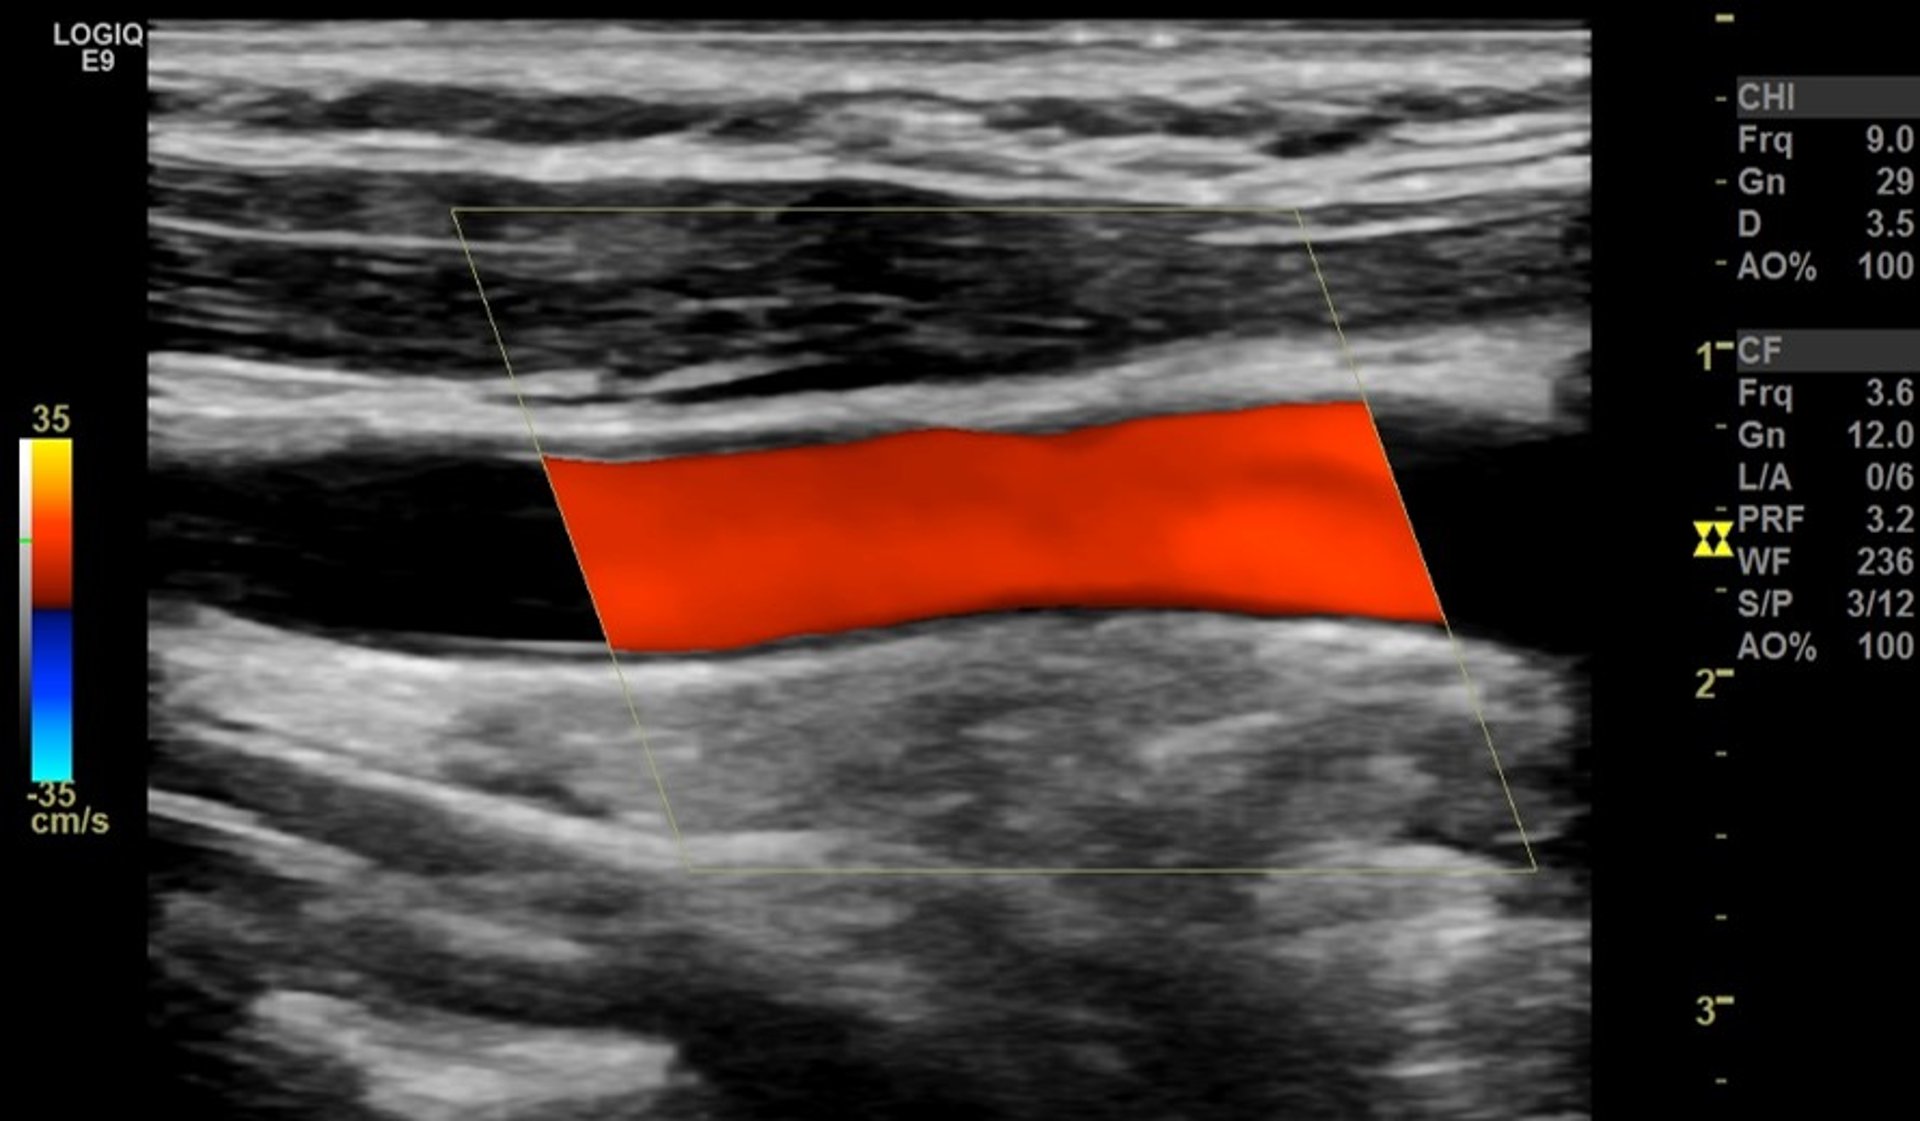

Ecografia color Doppler dell’arteria carotide

La striscia rossa rappresenta il flusso ematico normale senza ostruzioni attraverso una grande arteria del collo (arteria carotide comune), vista dal lato.

Immagine fornita dal Dott. Mustafa Mafraji